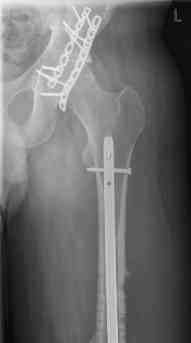

16 yr old boy, high energy motorcycle trauma trauma in July 2005 with:

- hip dislocation + acetabular fracture L

- distal femoral fracture L

- tibial shaft fracture L

- metatarsal fractures L

July 05

july 05: LISS femur, LCP plate tibia, double recon. plate post. acetabulum